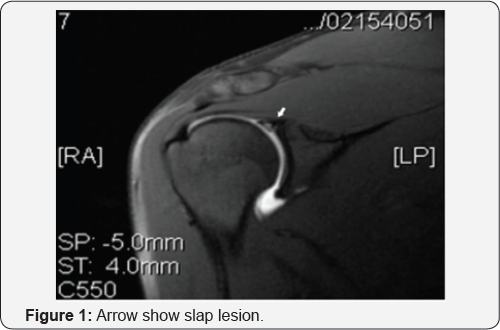

A study by Guanche and Jones [10] found only the O'Brien maneuver, the Jobe relocation test, and the apprehension sign to correlate with the presence of a SLAP tear found at arthroscopy. Even combined, none of these showed diagnostic specificity. It is recommended that multiple maneuvers be performed when examining a shoulder with a suspected SLAP tear, and the combined results may be suggestive but not definitively diagnostic. Imaging, like history and physical examination, can be suggestive but not completely sensitive. Plain radiographs, although indicated in the evaluation, are generally noncontributory. Magnetic resonance imaging, especially when performed with intra-articular gadolinium, can aid in the diagnosis ( Figure 1). Sensitivity is approximately 80% with specificity over 95% [11]. In short, the diagnosis of SLAP tears through all means can be a challenge. When history, examination, and imaging all suggest the diagnosis, then it is reasonable to pursue definitive treatment via arthroscopy.